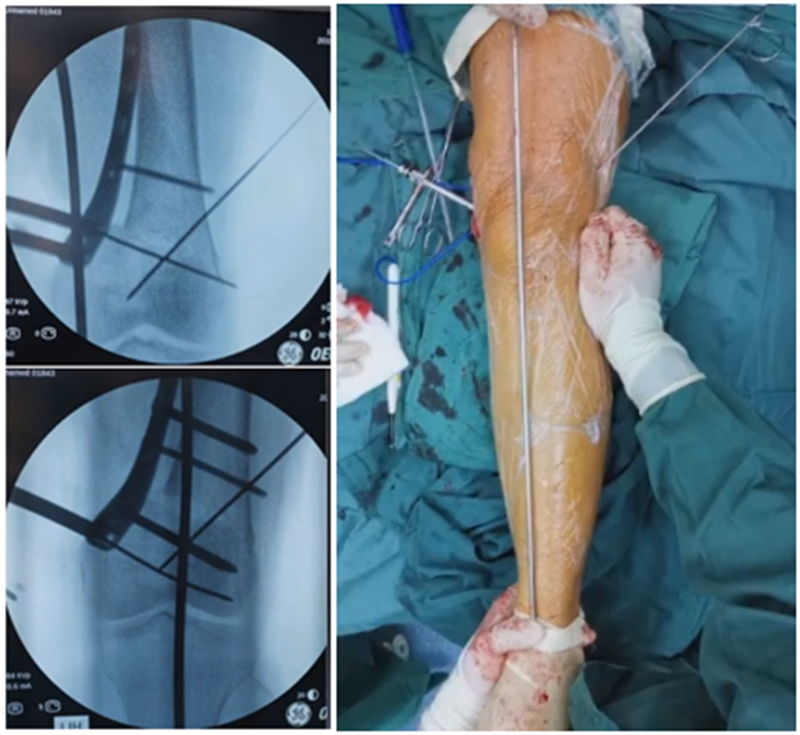

对于术中合页骨折,但非常不稳定、无法控制力线的情况,可以由外侧向股骨外髁打入一枚2.0的克氏针,因为克氏针具有一定弹性,相当于重建合页临时稳定性,在此基础上再去调整力线,做固定。

近端螺钉松开,调整力线,重新固定后,在外侧加小钢板抗旋。

术后10周复查,力线较好。